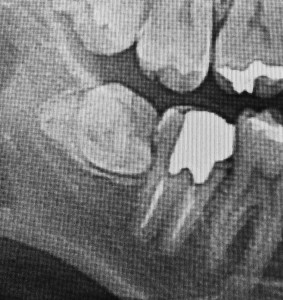

斜めに生えた親知らずは、奥歯との間に汚れがたまり、歯周病や虫歯を引き起こします。

親知らずは、口の中からはほとんど見えてないことも多いですが、骨からは外に出ていて、手前の奥歯に引っかかっている事が多いです。

引っかかった親知らずは上から歯茎が乗っかり、隙間だらけでとても汚れがたまる “不潔域” となってしまいます。